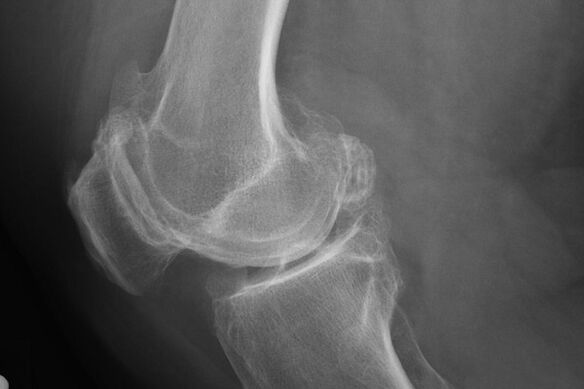

In der Regel tritt die Diagnose der Krankheit in diesem Stadium zufällig während eines Radius X auf. Der Arzt kann einige Unregelmäßigkeiten auf dem Knorpel sehen. Es ist auch möglich, das Licht zwischen den Teilen der Verbindung zu verengen.

X -Ray hilft dabei, die Abweichungen im Knorpel zu identifizieren.

Nach der Untersuchung verschreibt der Arzt die Radiographie des Patienten. Dies ist die Hauptmethode zur Diagnose der Arthrose des Kniegelenks eines beliebigen Grades.

X -Ray gibt dem Arzt eine Vorstellung von den Änderungen, die im Knorpel des Gelenks auftreten. In einigen Fällen kann die Anfangsphase jedoch auf dem Foto nicht definiert werden.

Bei Bedarf kann der Arzt einen wiederholten Durchgang einer X -Strahl -Tomographie oder eine berechnete und Magnetresonanztomographie verschreiben.